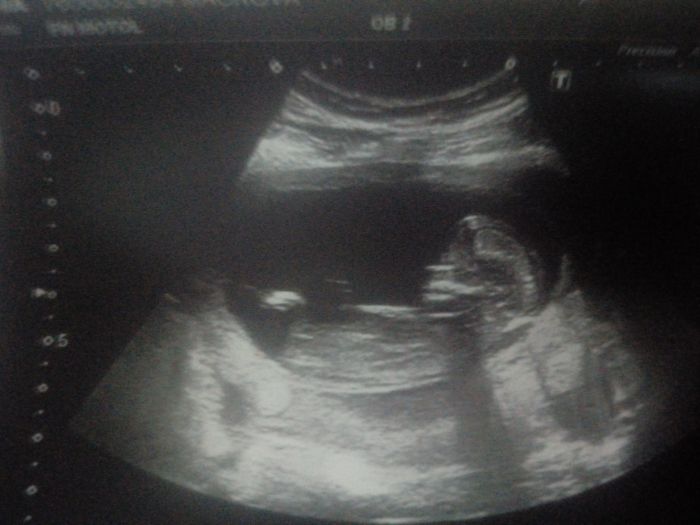

Holky tak se mi podařilo vyfotit fotku a připojit telefon k počítařče, no technický talent ze mě nebude.

[1017466] Jů Luci, to už je krásný mimin:-))ty jo, neskutečný, jak z jedné tečky za pár týdnů vyroste toto:-)

[1017467] No to mi povídej a to jsme prý měly štěstí, že tam fotky fakt nedávají, ale jak tam byla se mnou dcera, tak jsme jí dostaly. No jsem ráda, přeci jenom je to lepší přístroj, jak má můj gyndař. A to si vem, že prvka uvidím zítra znovu, jdu na gyndu. A budu mít průkazku. A tohle je třeba i můj motor, že se koukám dopředu a prostě se snažím si nepřipouštět, že by něco mohlo být blbě.